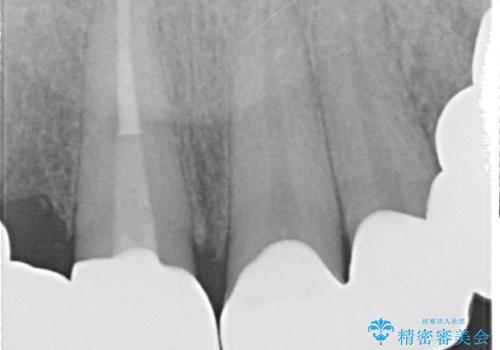

根尖病変が認められる歯は再根管治療を行い、歯根が破折していた左上4は抜歯しました。

インプラントは希望されなかったため、左側は1番から7番のロングスパンブリッジによる補綴を行いました。

今回用いたオールセラミッククラウンは、ジルコニアフレームという白い素材の上にセラミックを盛っているため審美性が非常に高いのが特徴です。

またジルコニアは人工ダイヤモンドの材料にも使われているほど高い強度を持っており、そのためオールセラミッククラウンは審美性だけでなく、奥歯やブリッジの補綴も可能とするクラウンです。